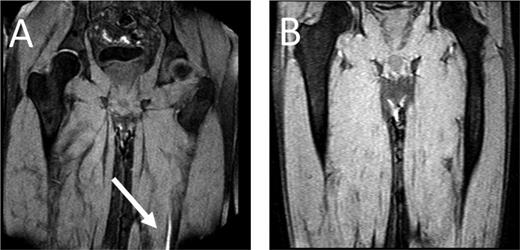

MRDTI of patient from case 1 (A): the white arrow indicates the fresh thrombus in the popliteal vein of the right leg. For contrast, B depicts the MRDTI of a patient with residual thrombosis in the left popliteal and femoral vein: no DTI signal is present.

As for our patient, his Wells score for DVT indicated “likely probability” (total of 2 points, 1 point for “calf enlargement >3 cm compared with the other site” and 1 point for “pitting edema”), indicating that a D-dimer test could definitely not be used for ruling out DVT.6,20 Because the patient fulfilled all inclusion and none of the exclusion criteria for the Theia study, he was referred for MRDTI, which showed a clear signal in the right popliteal vein (Figure 1), confirming the diagnosis of recurrent ipsilateral DVT. After 6 months of treatment, a reference CUS was performed and showed persistent incompressibility of the right popliteal vein.